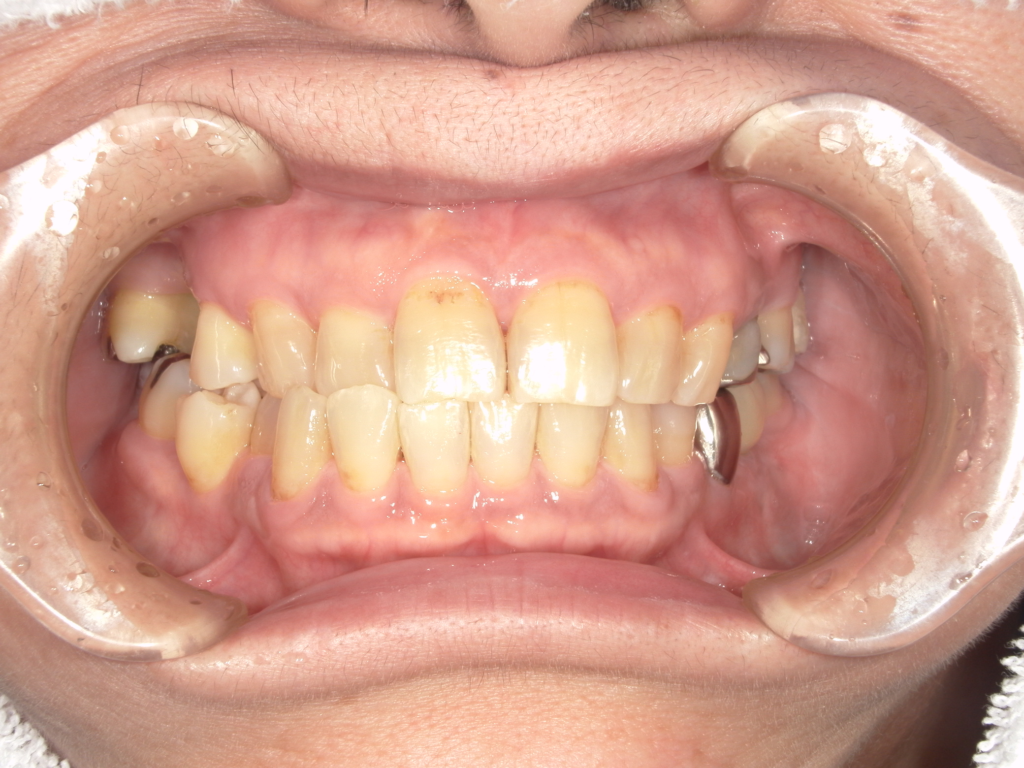

Y様インプラント実例 #44

左の上下の奥歯をインプラントで治療しています。

左下の奥歯は歯を抜くのと同時にインプラントの埋め込みを行っています。

被せものは上下、セラミックスで作っています。

治療前

治療後